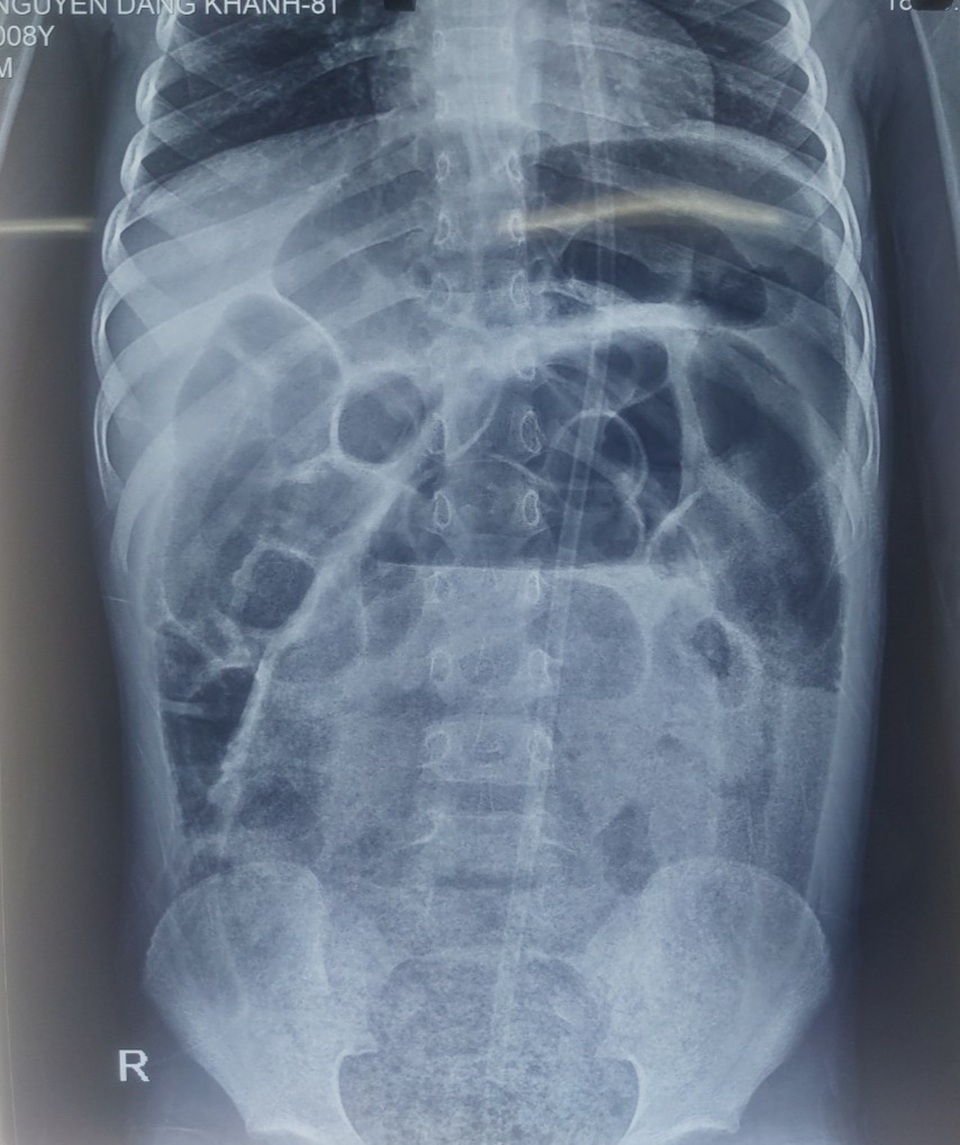

Tại khoa Phẫu thuật nhi, các bác sĩ thăm khám thấy trẻ bụng trướng căng, quai ruột nổi, bệnh nhi nôn dịch nâu bẩn, không đại tiện. Bóng trực tràng rộng, phía trên có khối phân to làm gấp đại tràng, dùng sonde không đẩy lên được để thụt tháo. Chụp X-quang quai ruột giãn to, chứa nhiều phân.

Hình ảnh X-quang các quai ruột giãn to và chứa nhiều phân ở cháu bé